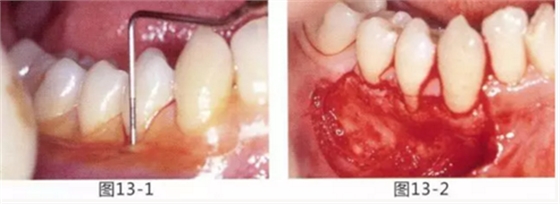

圖13-1 使用碘溶液進行染色,頰側(cè)基本看不到角化牙齦,且無口腔前庭的狀態(tài)。

圖13-2 為了擴張口腔前庭,獲取附著齦而進行了游離齦移植術(shù)。受皮床一定不能發(fā)生移動,盡可能使厚度均等。

圖13-3 手術(shù)剛結(jié)束的狀態(tài)。通過骨膜縫合的褥式縫合將移植片固定,使其無法移動。

圖13-4 手術(shù)完成2年后的狀態(tài)。口腔前庭得到擴張,即使正在進行正畸治療,也沒有妨礙到清潔。